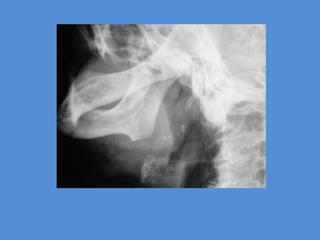

IMAGENOLOGÍA

-Radiografías con proyecciones

laterales y oclusión pueden

revelar un cálculo radiopaco.

-Las intraorales son más útiles.

-La ecografía no es tan útil.

Sialografía: Puede combinarse con rastreo por CT o imagen por

MRI, en especial debido a que los rastreos por CT son sensibles a las

sales de calcio.

Sialografía: Con el rayo central perpendicular al plano del chasis, se

dirige hacia la intersección del plano mediosagital y de un plano

coronal que pase por los segundos molares.